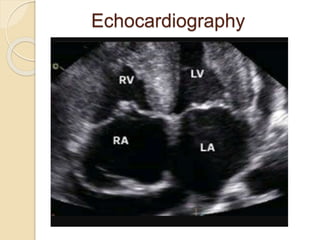

Echocardiography

Echo. Findings…….

 Transthoracic 2D- IAS can be imaged

from apical and subcostal four

chamber view

 Subcostal view is best

 Echo drop out in mid portion for ASD

secundum

 Color doppler imaging shows directly

flow from LA to RA

Echo. Findings…….  Transthoracic2D- IAS can be imaged from apical and subcostal four chamber view  Subcostal view is best  Echo drop out in mid portion for ASD secundum  Color doppler imaging shows directly flow from LA to RA